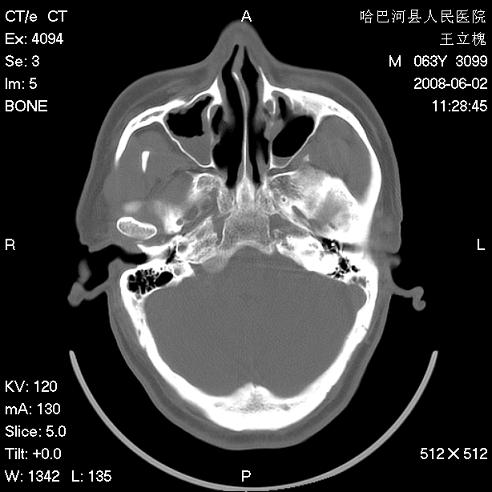

标题: CT13803:反复性鼻塞、流涕一年余 [打印本页]

标题: CT13803:反复性鼻塞、流涕一年余

副鼻窦炎,右上额窦积脓。左眼肌锥内见致密影,视神經受压

1.全组副鼻窦炎2.双侧上颌窦积液

1)全副鼻窦炎(左侧上颌窦黏膜下囊肿或息肉)。2)左眼眶肌锥内不规则小结节状软组织密度影;考虑为小血管瘤可能。建议行ct增强扫描检查。

全组副鼻窦炎,左侧肌锥内不规则形软组织肿块影,与眼外肌密度相当,左侧视神经受压,肿块与视神经及眼外肌分界清晰,眼外肌无增粗,眶壁无破坏,球后脂肪间隙不模糊,考虑良性改变,小血管瘤或神经源性肿瘤可能,建议增强扫描。

谢谢,增强扫描做了,眶内病灶与海绵窦同步明显强化,血管瘤